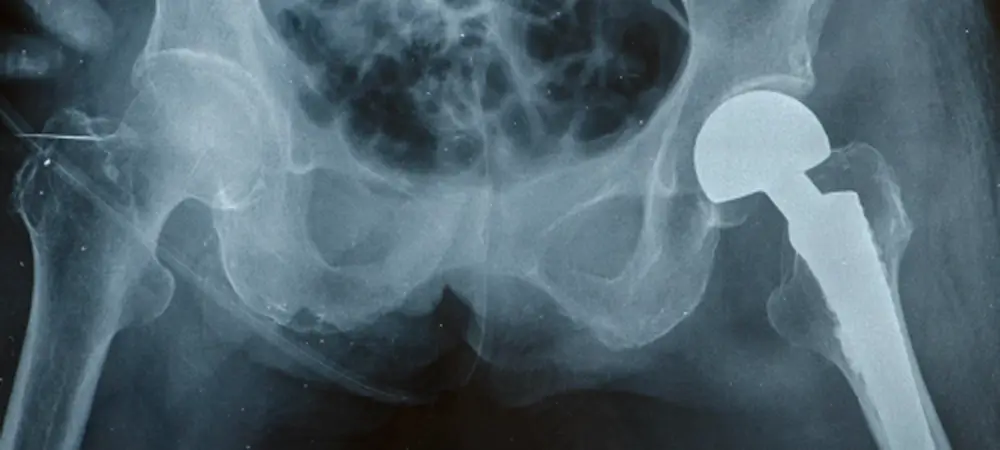

Did you know that approximately 50% of common orthopedic implants, such as hip replacements, are now made from medical-grade titanium?

One of its primary uses is in the manufacture of orthopedic implants for joints (hips, knees, etc.) and dental implants due to its biocompatibility and unique ability to bind with bone and living tissues (known in the medical world as osseointegration). Also, the non-ferromagnetic properties of titanium make it an ideal choice for implants since patients can safely receive MRI or MRA exams.

Medical grade titanium is shaping the future of healthcare in profound ways. Its exceptional biocompatibility, corrosion resistance, and strength-to-weight ratio make it an indispensable material in medical applications. From orthopedic implants to dental prosthetics, surgical instruments, and diagnostic equipment, titanium's versatility and reliability are transforming the landscape of medical manufacturing.